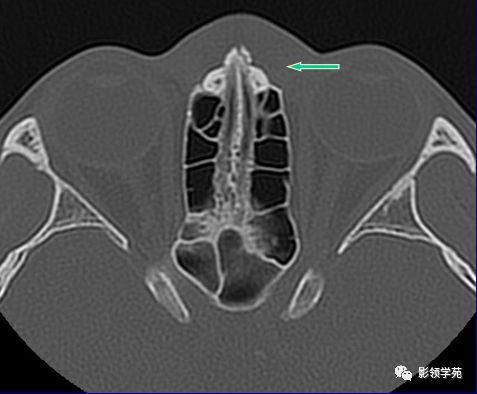

右侧鼻骨骨折

左上颌骨额突骨折

双侧鼻骨骨折

双侧上颌骨额突骨折

鼻中隔骨折